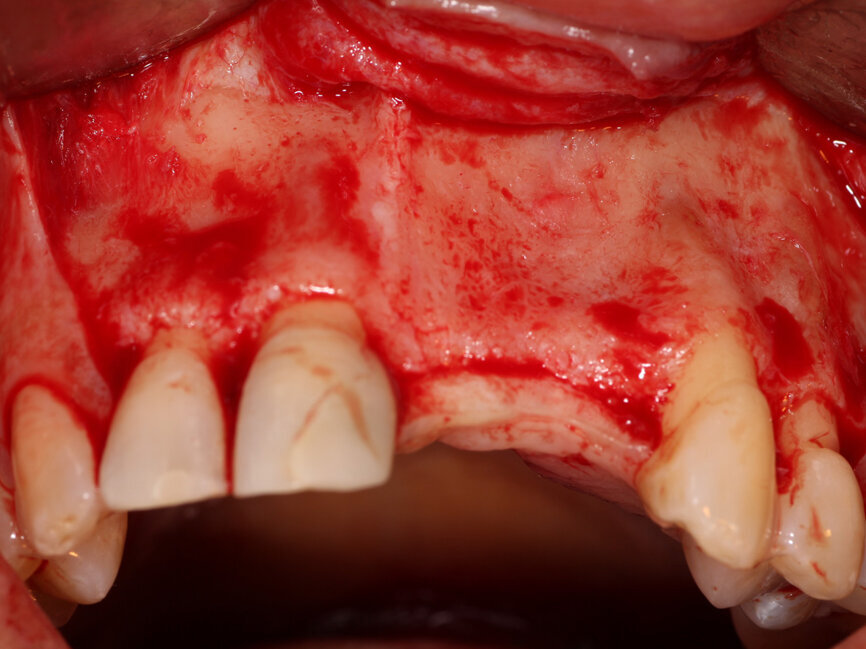

A 52-year-old male patient presented missing the left central and lateral maxillary incisors with a desire to have implants to replace the missing teeth and a fixed prosthetic approach. The patient indicated that the teeth had been extracted eight years before, and clinical examination noted a deficient facial aspect of the ridge at the extraction sites and healthy soft tissue (Fig. 1). A cone-beam CT (CBCT) was taken and evaluated. Cross-sectional views of the edentulous space confirmed inadequate width of the ridge in the facial-palatal dimension to house implants at the adjacent sites (Fig. 2). The patient was informed of the clinical findings and a discussion on augmenting the site with an osseous graft would be necessary for implant placement. As insufficient bone would not permit simultaneous implant placement at the time of grafting, the patient was informed that a healing period of four to six months would be needed between graft placement before implants could be placed. This would then be followed by a four- to six-month period to allow the implants to osseointegrate before any restoration could be placed on the implants. The patient agreed to treatment and was appointed.

Fig. 1: Deficient facial aspect to the anterior maxilla resulting from resorption following tooth extraction. (Photos provided by Dr. Arun K. Garg; Dr. Gregori M. Kurtzman; Dr. Renato Rossi Jr.; and Dr. Maria del Pilar Rios)